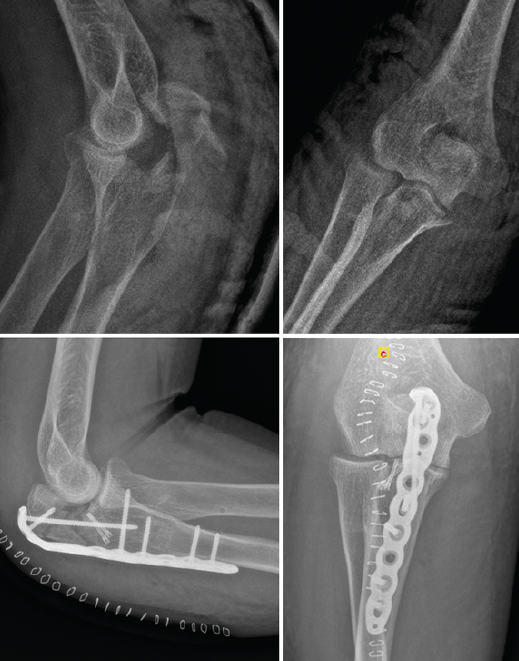

Figura 5. Radiografías simples de codo en proyección anteroposterior y lateral. En estas radiografías puede apreciarse una luxación posterolateral de un codo izquierdo, además de fractura de la cabeza del radio y fractura de la punta de la coronoides.

3. Radiografías simples de codo en proyección anteroposterior (AP) y lateral (Figura 5).